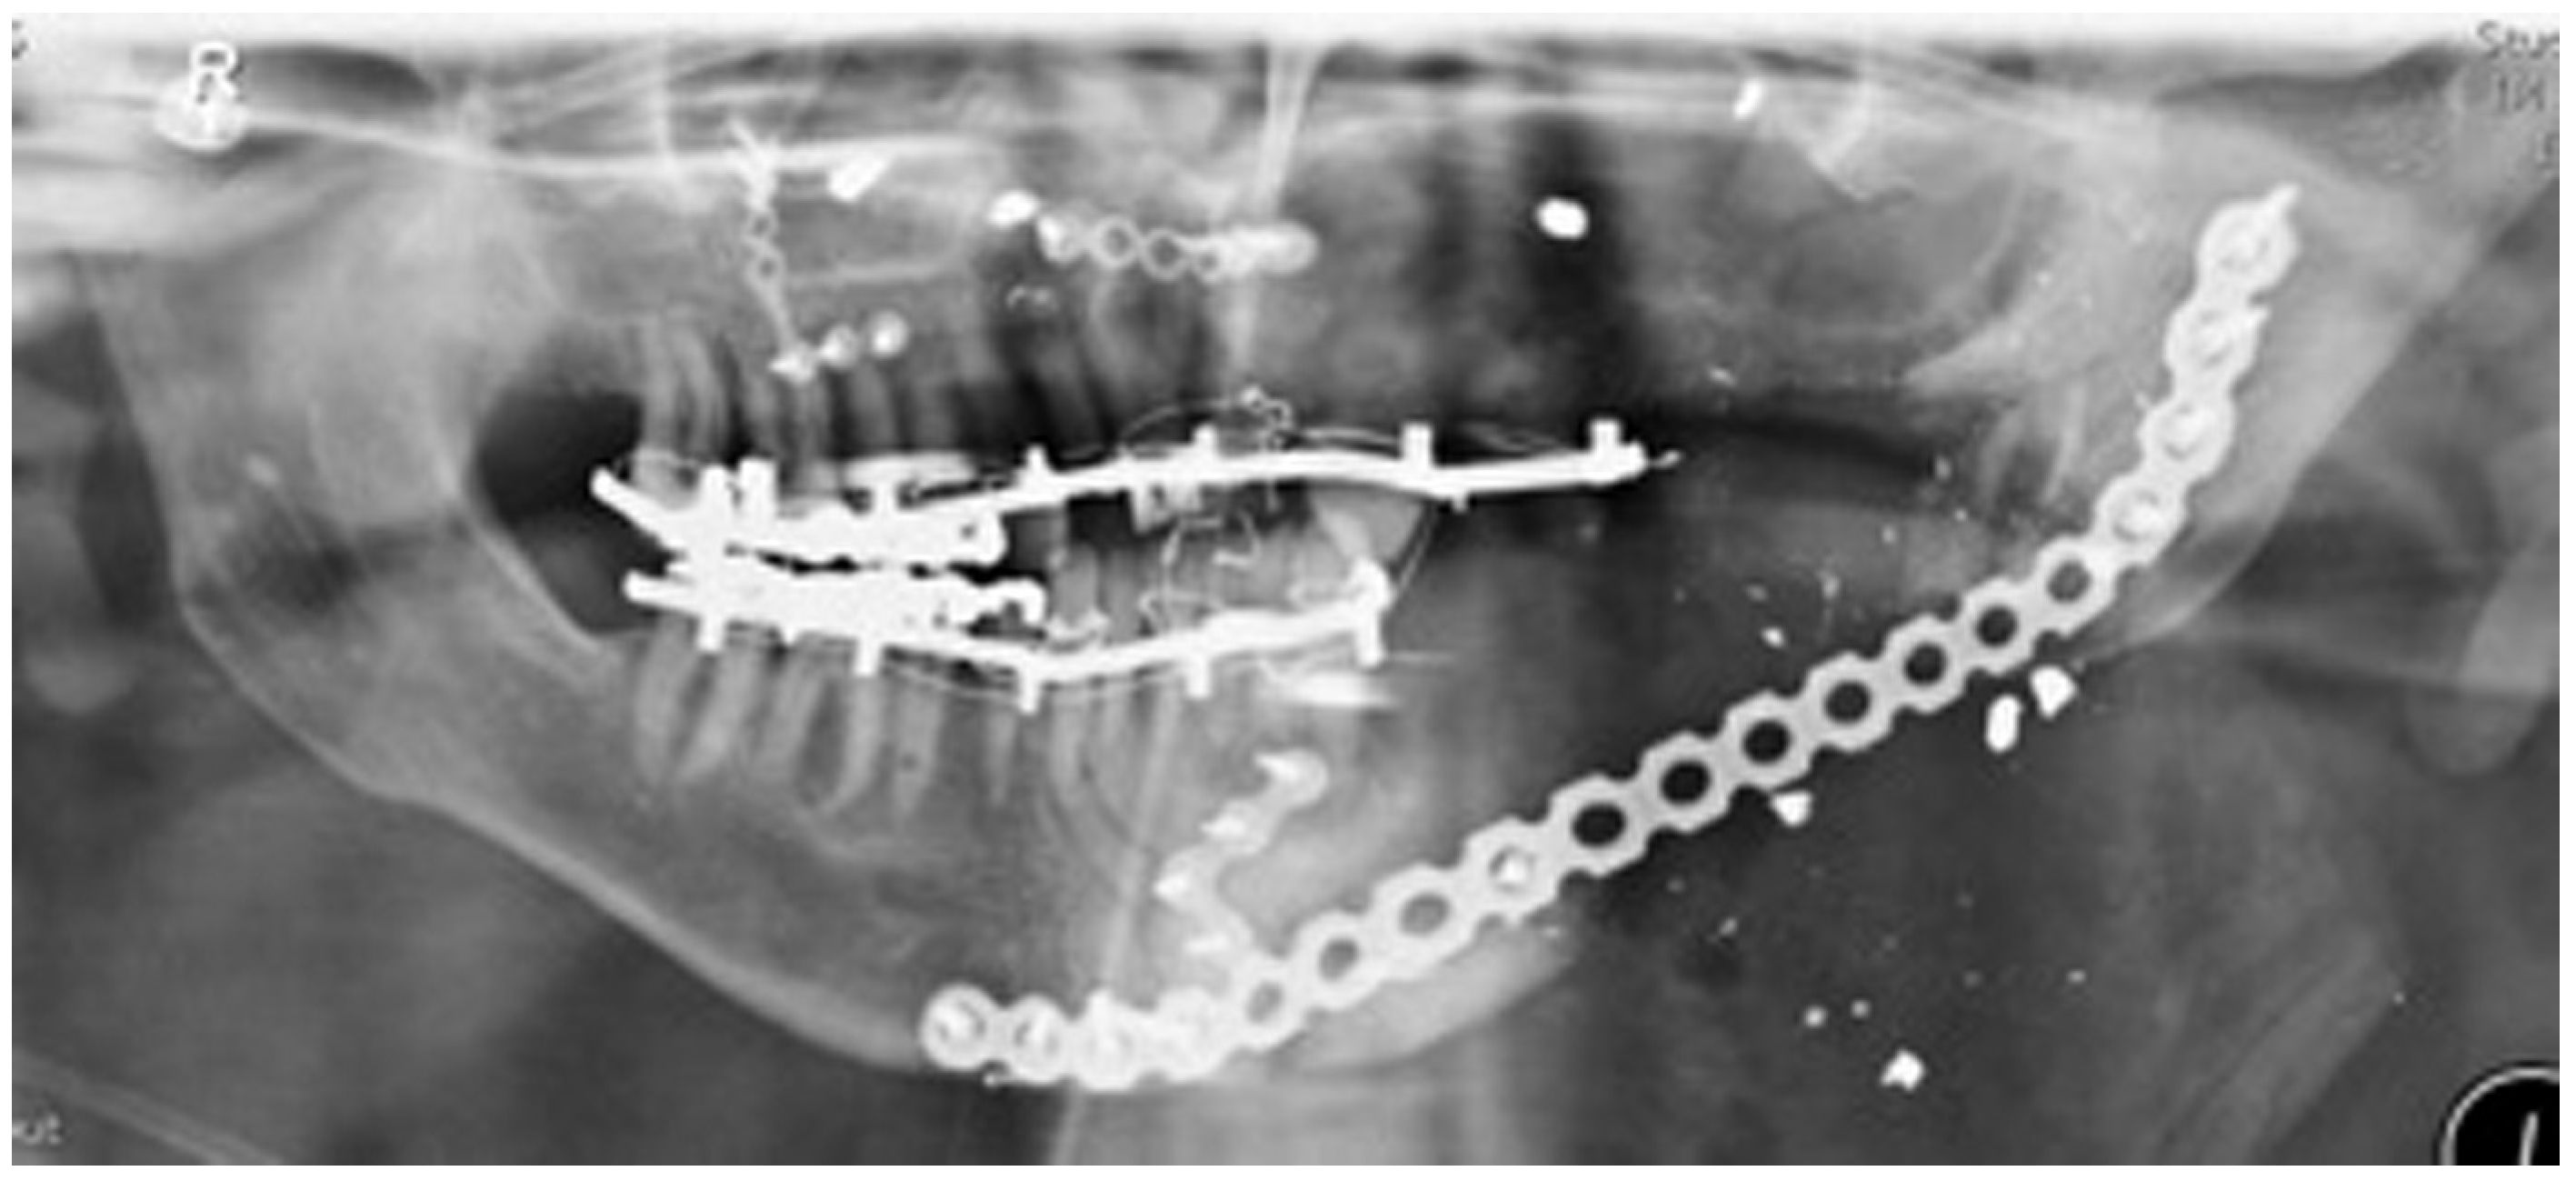

Staged reconstruction was defined as when the reconstruction with the free bone graft was performed as a secondary procedure. This secondary procedure was only performed when the oral mucosa had healed intraorally, sealing the mouth from the defect and the neck. A loadbearing locking mandibular plate was used to maintain the three-dimensional position of the bone and thus the occlusion (see Figure 1, Figure 2, Figure 3, Figure 4, Figure 5, Figure 6, Figure 7, Figure 8, Figure 9, Figure 10 and Figure 11).

Figure 11.

Orthopantomography(OPT) showing free bone graft placed in segmental defect.

All the reconstructions in our study were staged. The average length of the free bone grafts was 6.7 cm (range: 6.0–7.1 cm) and the average height of the free bone grafts was 2.3 cm (range: 1.0–3.2 cm). The follow-up period was between 6 and 108 months (average 30 months). Twelve patients had no complications at the recipient site and two patients had minor wound breakdown extraorally, which resolved with antibiotics. One bone graft was lost due to infection. In Birmingham, two patients had been dentally rehabilitated with implants. Another four patients have been scanned and are awaiting dental implant placement. No patient in Florida was dentally rehabilitated with dental implants.

The three-dimensional shape and position of the mandibular fragments was maintained by a strong locking plate, while the oral mucosa healed and the pathology was awaited. The same plate was then subsequently used to secure the free bone graft.